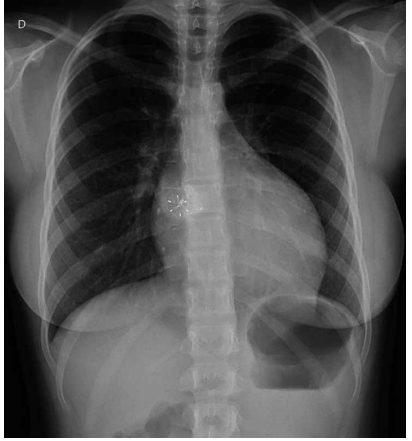

Considere a imagem a seguir.

Essa radiografia de tórax diz respeito a qual cardiopatia congênita?

Coarctação de aorta.

Estenose valvar pulmonar.

Comunicação interatrial.

Insuficiência mitral.

Estenose de artéria pulmonar direita.